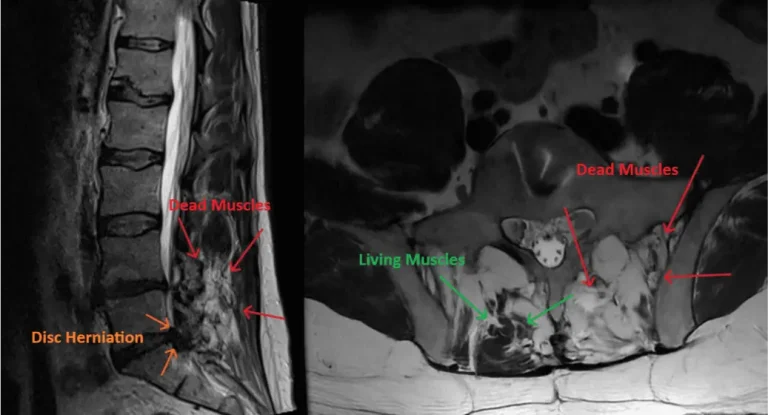

MRI showing disc herniation and muscle condition with labeled dead and living muscles.

8) Severe Post-Operative Pain

Excessive postoperative pain always occurs after laminectomy due to muscle trauma and necrosis (death of muscles). During laminectomy the muscles are torn off the spine by the surgeon in order to get down to the lamina. The dying muscles cause severe postoperative pain that always requires opioid painkillers and muscle relaxers. Opioid painkillers are highly addicting, cause tolerance, abuse and even death from breathing failure.